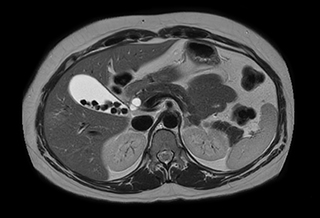

Free breathing abdominal MRI with VitalEye

Ascites can be hard to image, but excellent result is obtained with Ingenia Ambition. This high resolution image demonstrates the high quality that can be obtained with VitalEye and the patient just breathing normally. The acquisition time is fast thanks to the accuracy of the respiratory gating with VitalEye** and it also saves the time needed to put a respiratory belt on the patient.

3D T2 with VitalEye